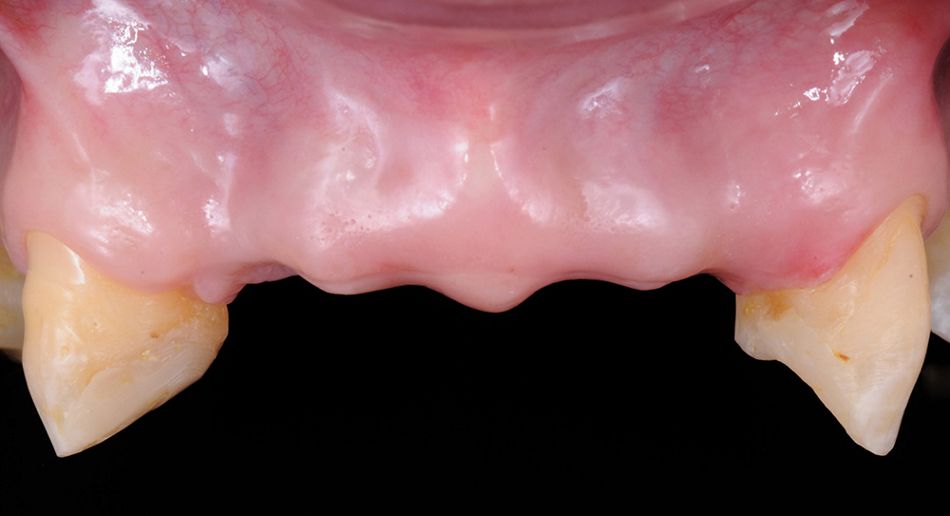

The clinical examination showed a significant horizontal deficiency of the anterior(Figs. 1, 2). Panorex Rx (Fig. 3). Study models mounted on a semi-adjustable articulator were taken and a diagnostic wax-up of the four incisors was made with a modeled gingiva (Fig. 4) to provide an idea of the amount of tissue to be regenerated. In the axial slices and the 3D reformatted CT images, the lack of bone in the horizontal and vertical dimensions could be evaluated precisely. A stepwise surgical approach was planned: in a first step, a GBR procedure would be performed. In a second step, two submerged implants should be inserted and, if necessary, an additional GBR procedure performed. In a third step, implants should be uncovered together with a soft tissue augmentation. The initiation of the prosthetic phase was planned 30 days after the implant activation surgery.

Two weeks later, sutures were removed, and the temporary fixed screw-retained partial prosthesis was placed (Fig. 18). Teeth 13 and 23 were prepared for full crowns (Fig. 19). As the patient was under orthodontic treatment, it was decided to make a new resin fixed screw-retained prosthesis in order to have ideal conditions for the placement of the two implants to replace teeth 24/25, and to delay the definitive porcelain restorations once the case was completed (Fig. 20).